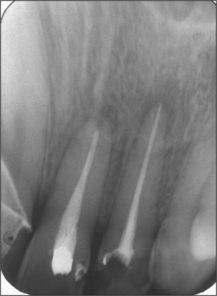

Ideally, there should be complete regeneration of periapical bone and an intact lamina dura after surgical endodontics (Fig. 6.15). However, a persistent apical radiolucency after surgery does not necessarily indicate an unsuccessful outcome. The capacity for bone regeneration diminishes with age, and sometimes surgical endodontics is successful even though a bone defect persists at the apex of the affected tooth. This is the main reason why the criteria for success should not be based solely on radiographic appearance.

image

Fig. 6.15 Radiographs taken at 1 week and 6 months after apicectomy and retrograde root filling of the upper left central and lateral incisors. The bone has not returned completely to normal density at 6 months, but a lamina dura has reformed around the apices.